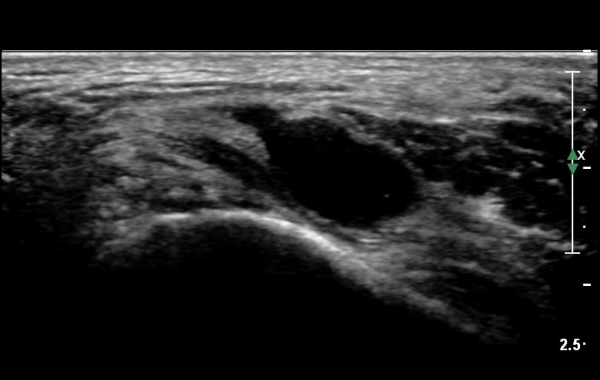

¹ß¸ñÅͳΠȾ´Ü¸é°Ë»ç¿¡¼­ ³»Ãø º¹»ç»À ³»Ãø¿¡ Èİæ°ñ°Ç, ¹ß°¡¶ô±¼°î°Ç°ú ¾öÁö¹ß°¡¶ô±¼°î°Ç

»çÀÌ¿¡¼­ Èİæ°ñ½Å°æÀÌ °üÂûµÇ°í ½Å°æÀÇ Ç¥Ãæ¿¡ µ¿¸Æ°ú Á¤¸ÆµéÀÌ °üÂûµÈ´Ù(»çÁø 1).